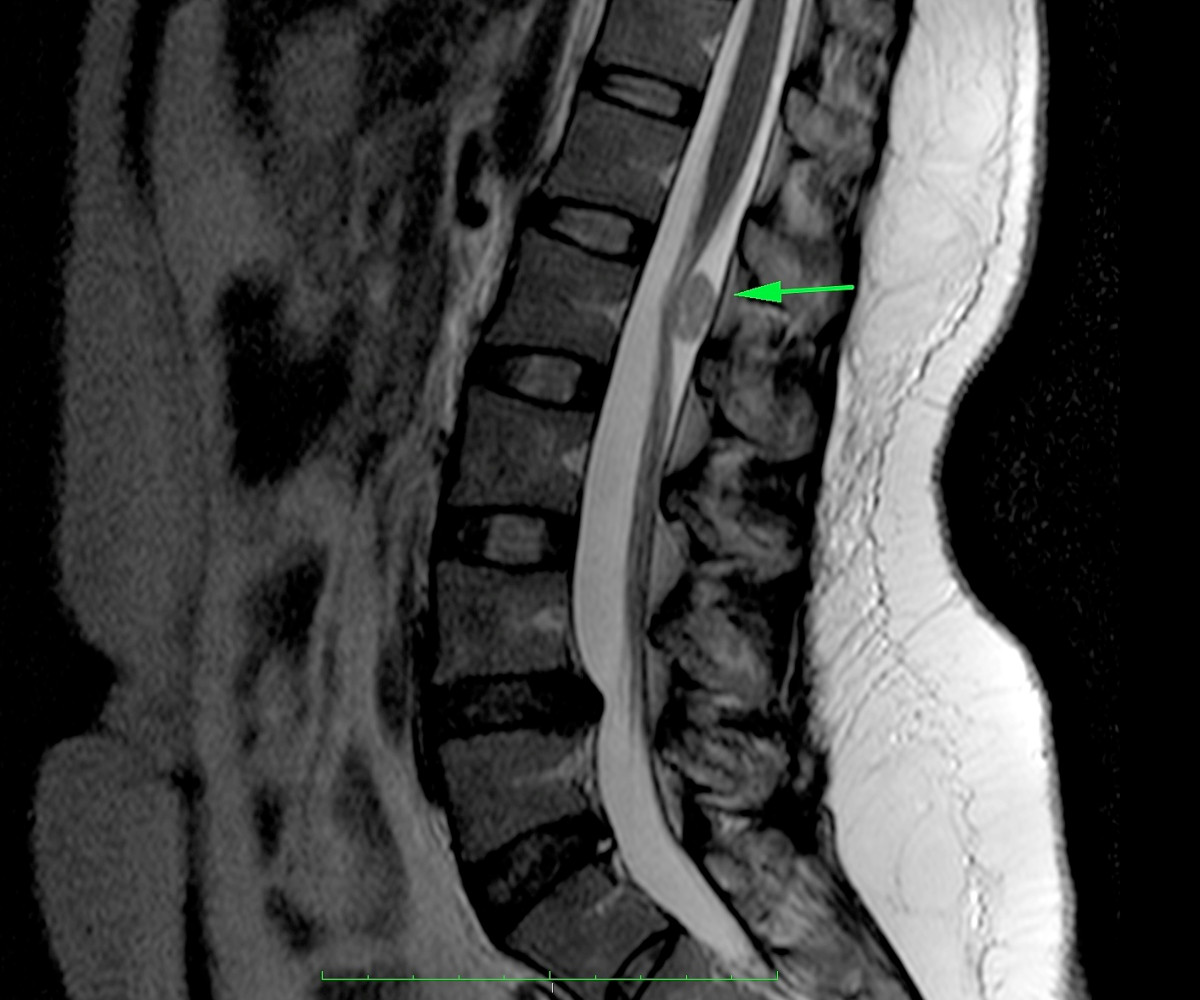

Mujer de 35 años, con parestesias en extremidades inferiores de predominio derecho y dolor a la flexión. Se realizaron estudios de imagen, donde se aprecia una lesión referida de cono medular (se anexan estudios de imagen). Se realizó resección tumoral.